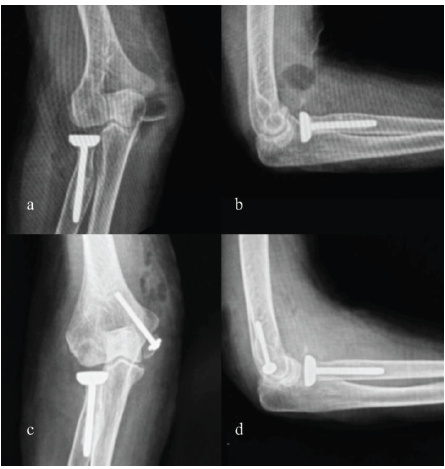

(CC screw) A 70-year-old female sustained fall onto her left elbow. The patient was previously operated with radial head replacement. Examination revealed swelling, pain, and limited flexion. Radiographs demonstrated a large medial epicondyle fragment and a radial head implant. The fracture was fixed with a single 4.5 mm CC screw after anatomical reduction. Union was evident at 14 weeks; she regained a 0–110° arc of motion, with mild persistent stiffness but independence in daily activities (Fig. 5).

Figure 5: Pre-operative and post-operative X-rays right elbow (a) pre-operative X-ray right elbow anterior-posterior (AP) view, (b) pre-operative X-ray right elbow lateral view, (c) post-operative X-ray right elbow AP view, (d) post-operative X-ray right elbow lateral view.